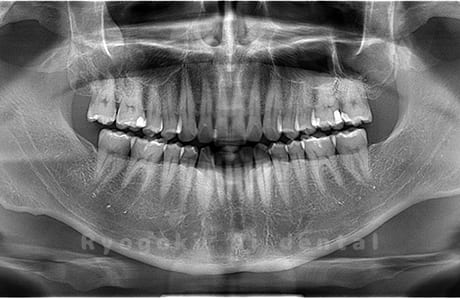

水平埋伏の親知らず

歯茎の中で完全に横に生えてしまうタイプです。

この親知らずを水平埋伏智歯と言います。このタイプはほとんどが下顎のケースです。真横に生えているので抜歯の際は難易度が高く2~3つに砕いて分けて抜歯をします。